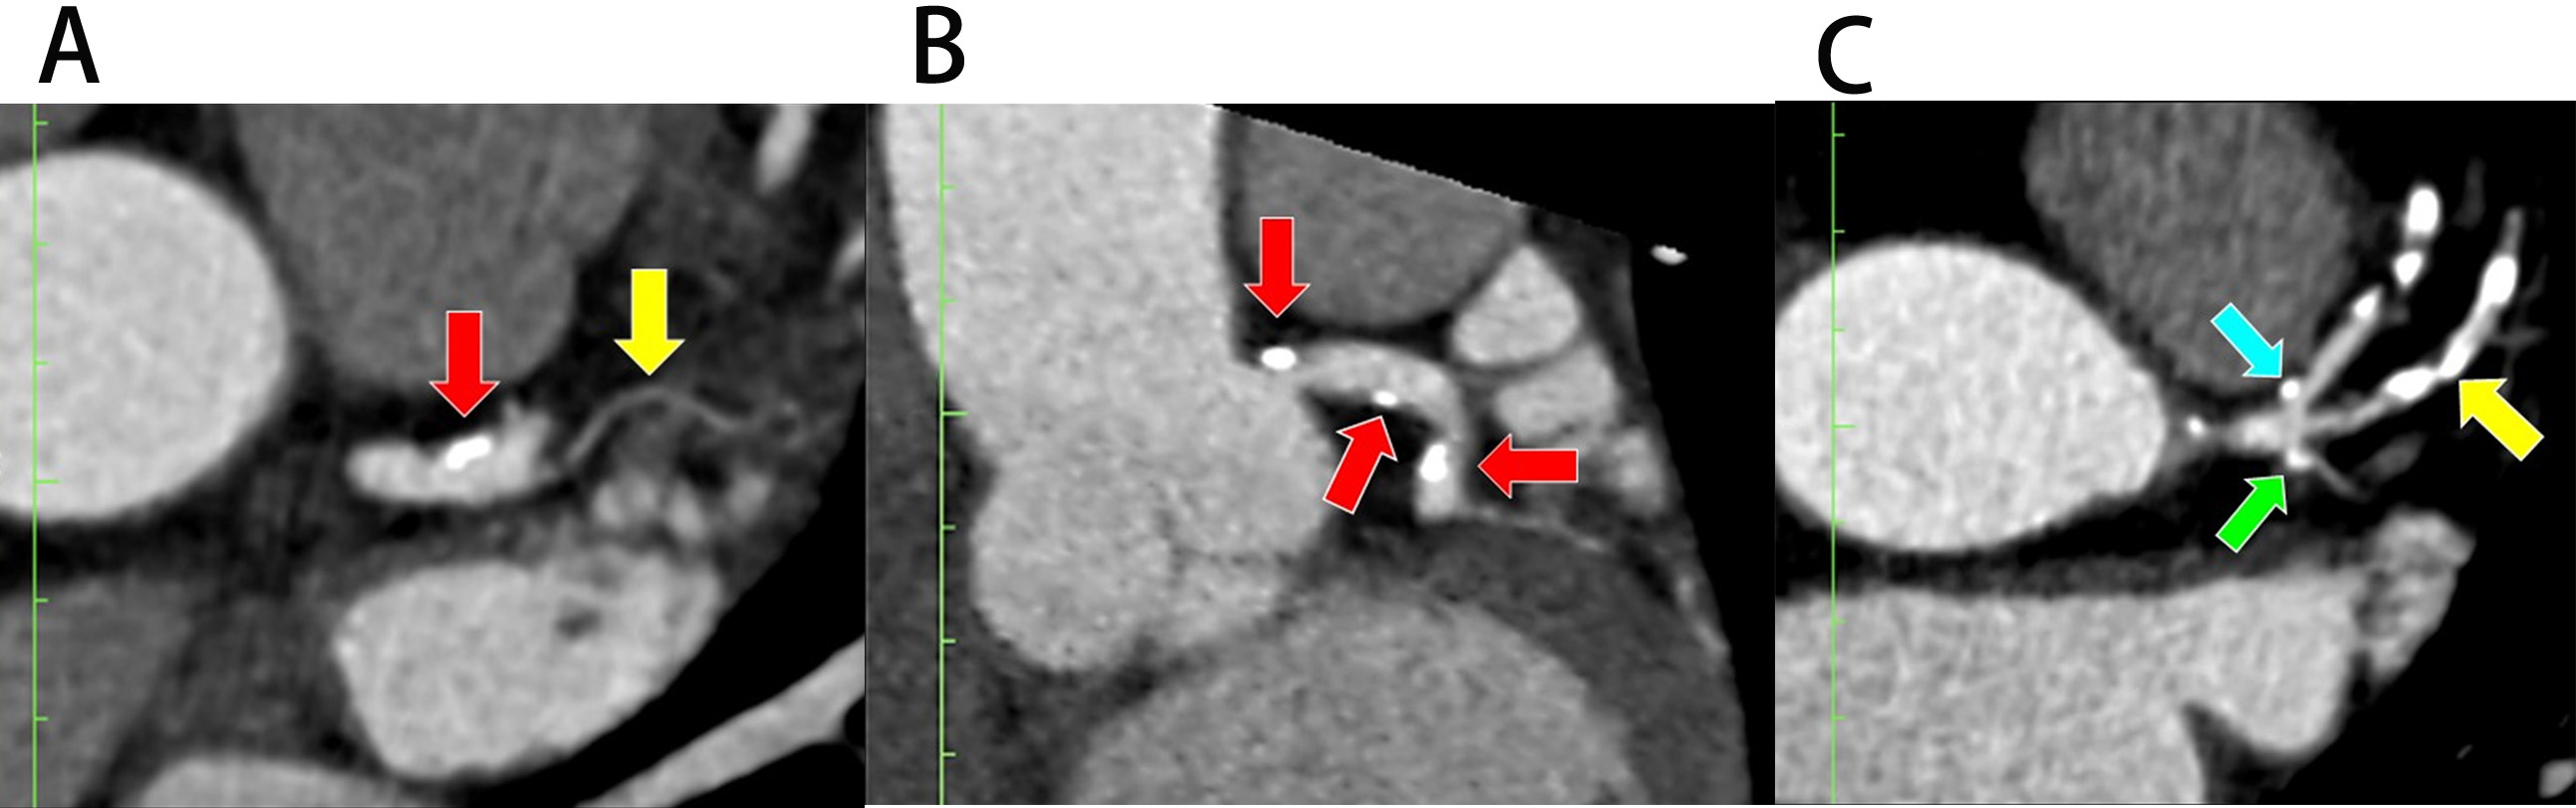

Analysis of the LBR in this study was made according to the techniques described by Beton et al. (2017) [21]. Briefly, identification of the plaque location in the LMCA, proximal left anterior descending (pLAD), and proximal left circumflex (pLCx) were made at a specific distance as illustrated in the schematic diagrams (Fig. 2A, Fig. 3A, and Fig. 4A). The LMCA was taken as the parent vessel, whereas the pLAD and pLCx arteries were considered as the daughter vessels. The analysis was made within a 10 mm distance from the distal end of the LMCA and within a 10 mm distance from the ostia of the daughter vessels [21]. Images were reconstructed in a multiplanar reconstruction (MPR) format and analysed using the Centricity Picture Archiving and Communication System, Universal Viewer Version 5.0 (GE Healthcare, Chicago, IL, USA) (Fig. 2B–D, Fig. 3B, and Fig. 4B). A consistent setting was used to analyse the presence of the RI and LBR [20]. Those patients with the presence of RI were categorised into the “Experimental” group, and their data were analysed against patients with the absence of RI were categorised into the “Control” group (Fig. 1).

Fig. 3. The demarcation and identification of the proximal left anterior descending artery. (A) Schematic diagram of the pLAD at a distance of 10 mm from its ostium (blue line). (B) The pLAD in MPR image (axial view). Yellow dots indicate the marking for the ostia of daughter vessels; “c” indicates the lateral wall, and “d” indicates the medial wall for pLAD. Ao, aorta; LMCA, left main coronary artery; pLAD, proximal left anterior descending artery; pLCx, proximal left circumflex artery; MPR, multiplanar reconstruction.

Fig. 4. The demarcation and identification of the proximal left circumflex artery. (A) Schematic diagram of the pLCx at a distance of 10 mm from its ostium (green line). (B) The pLCx in an MPR image (axial view). Yellow dots indicate the marking for the ostia of daughter arteries; “e” indicates the lateral wall, and “f” indicates the medial wall for pLCx. Yellow dots represent the marking for the ostia of daughter vessels. Ao, aorta; LMCA, left main coronary artery; pLAD, proximal left anterior descending artery; pLCx, proximal left circumflex artery; MPR, multiplanar reconstruction.

Plaque analyses in the pLCx and pLAD arteries were made within a 10 mm distance from their ostia (i.e., the pLAD ostium was marked with a blue dotted line and the pLCx ostium was marked with a green dotted line, Fig. 3A and Fig. 4A). The actual measurement that was taken using MPR images is shown in Fig. 2C. To investigate the preference of plaque formation in either walls of the daughter vessels, the pLCx and pLAD were further subdivided into medial (labelled “d” for pLAD and “f” for pLCx) and lateral (labelled “c” for pLAD and “e” for pLCx) walls (Fig. 3A,B, Fig. 4A,B). A plaque was identified as a hyperdense region within the arterial wall that can either show a calcified, non-calcified, or mixed appearance. The presence of atheroma in the LMCA, pLAD and pLCx were documented.